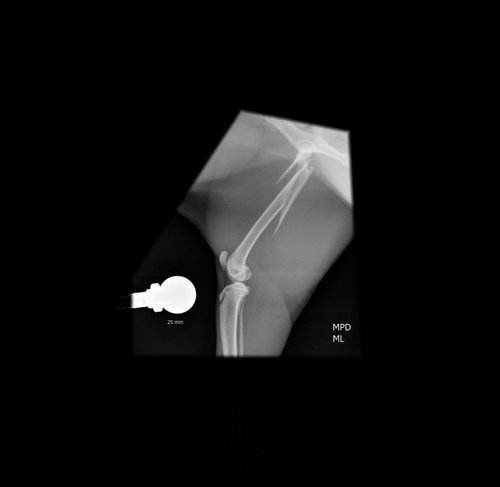

Meu nome é Jen, e sou tutora do pequeno Frederico, um gatinho muito querido de apenas 10 meses que está passando por um momento difícil. Recentemente, ele sofreu um acidente no dia (11/01) e fraturou o fêmur, uma lesão que o impede de se movimentar e está causando muita dor.